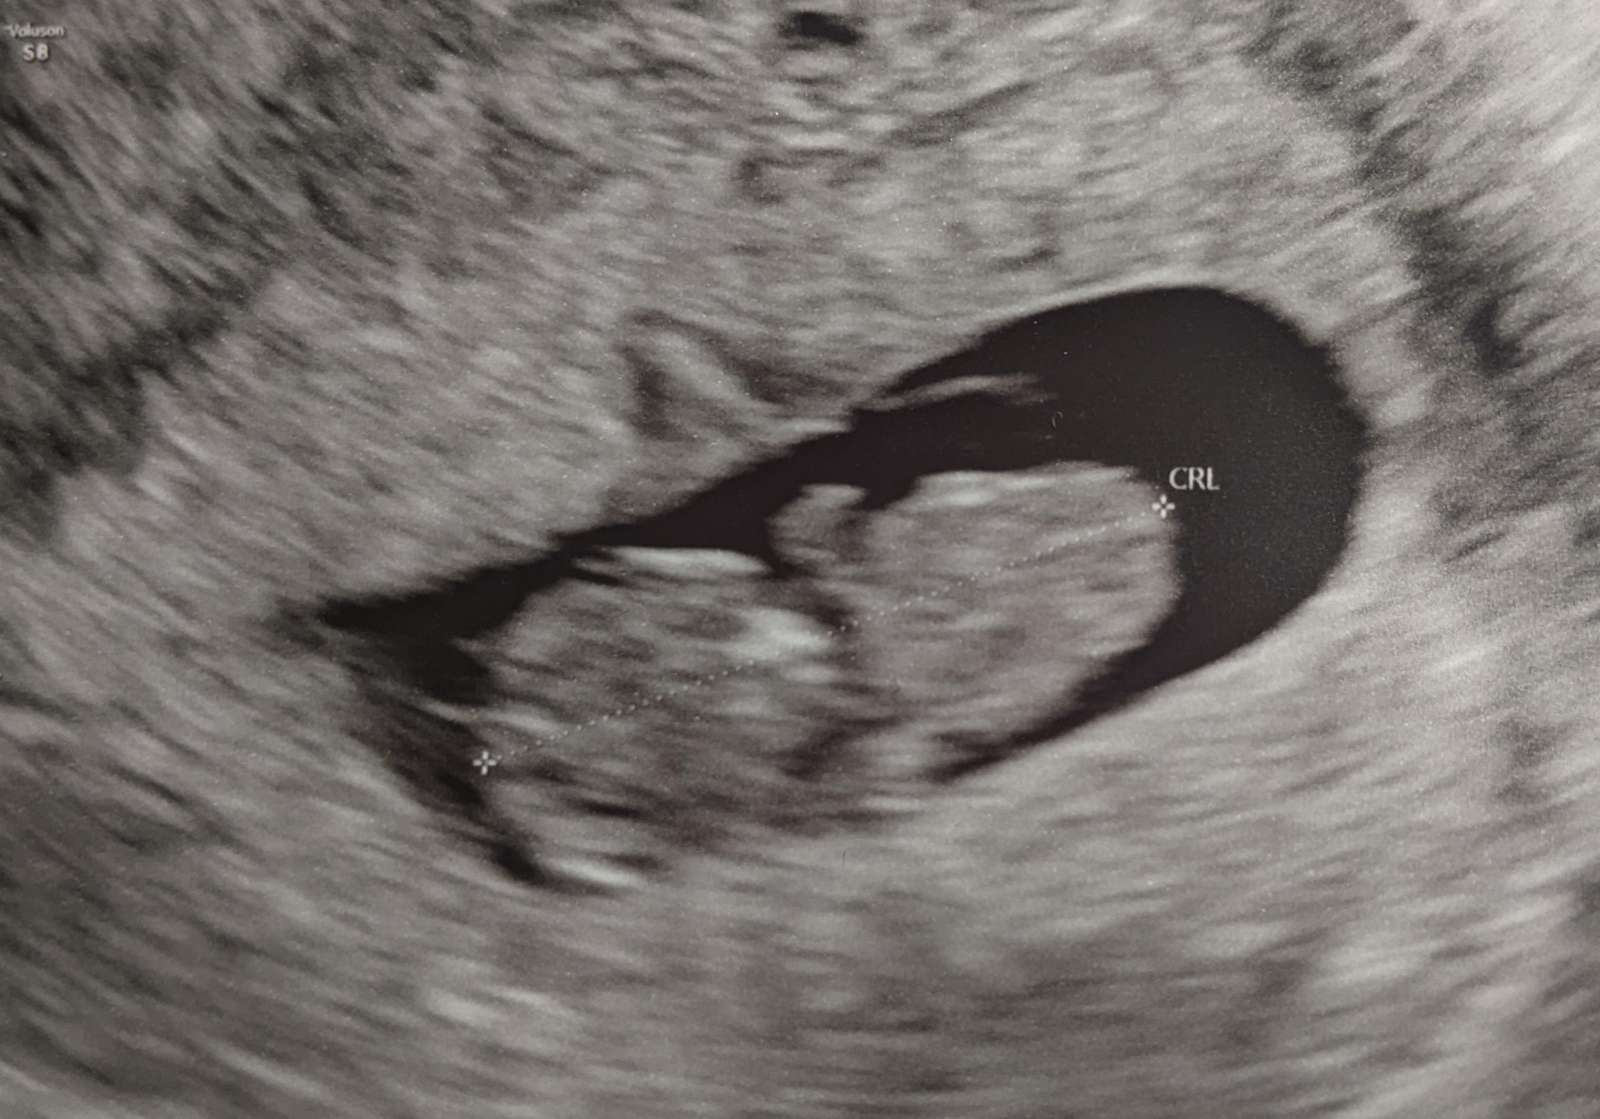

We had our ultrasound yesterday, at 9 1/2 weeks. And our baby is right on track! Heartbeat and size are perfect for 9 1/2 weeks, and it all looks good. I have little pictures and videos of the ultrasound. We saw him move his little arms and legs and wiggle around. So crazy! He's only an inch long right now, but it's wild that an inch long baby is just chilling in my squishy belly right now. That's nuts.